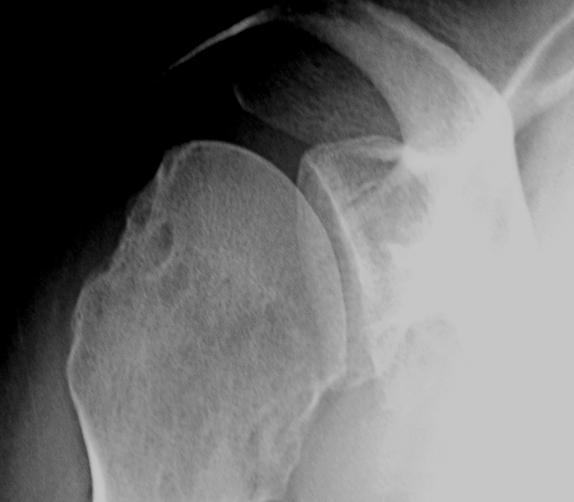

From orthosho.com

Shoulder Dislocation OrthoSHO What Is Shoulder Bankart Repair Surgery for a bankart lesion involves removing dead or damaged tissue and repairing the tear in the. what is surgical repair for a bankart lesion? They present with generalised shoulder pain. a bankart lesion repair is usually carried out arthroscopically (hey hole surgery) under general anaesthetic. Minimally invasive surgical procedure to repair a tear of the glenoid labrum. What Is Shoulder Bankart Repair.